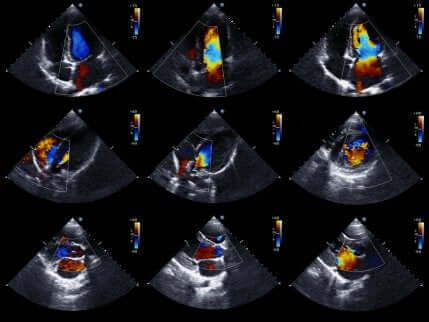

Echokardiogram

Echokardiogram (echo serca) lub sonogram serca pozwala lekarzom na bardziej szczegółowe badanie serca.

Echo serca jest bardzo popularnym testem medycznym. Dzieje się tak, ponieważ przedstawia ruchomy obraz serca. W ten sposób lekarz może ocenić stan komór serca i ich ruchy. Pozwala to potwierdzić lub wykluczyć niedokrwienie.

Ponadto ocenia się również rozmiar i siłę mięśnia serca oraz stan ścian jego komór. Warto zaznaczyć, że jest to nieinwazyjny test, który nie wiąże się z ryzykiem dla pacjenta. Jest tak, ponieważ do uzyskania obrazów serca wykorzystuje się ultradźwięki.

Jeśli lekarz zdecyduje się wykonać to badanie, to brak zaburzeń ruchowych w obrazie ściany serca pozwala ostatecznie wykluczyć niedokrwienie. Istnienie zaburzeń ruchowych nie jest unikalne w przypadku ostrego zespołu wieńcowego. Z tego powodu powinno się oceniać wspólnie wyniki wszystkich testów i objawy.